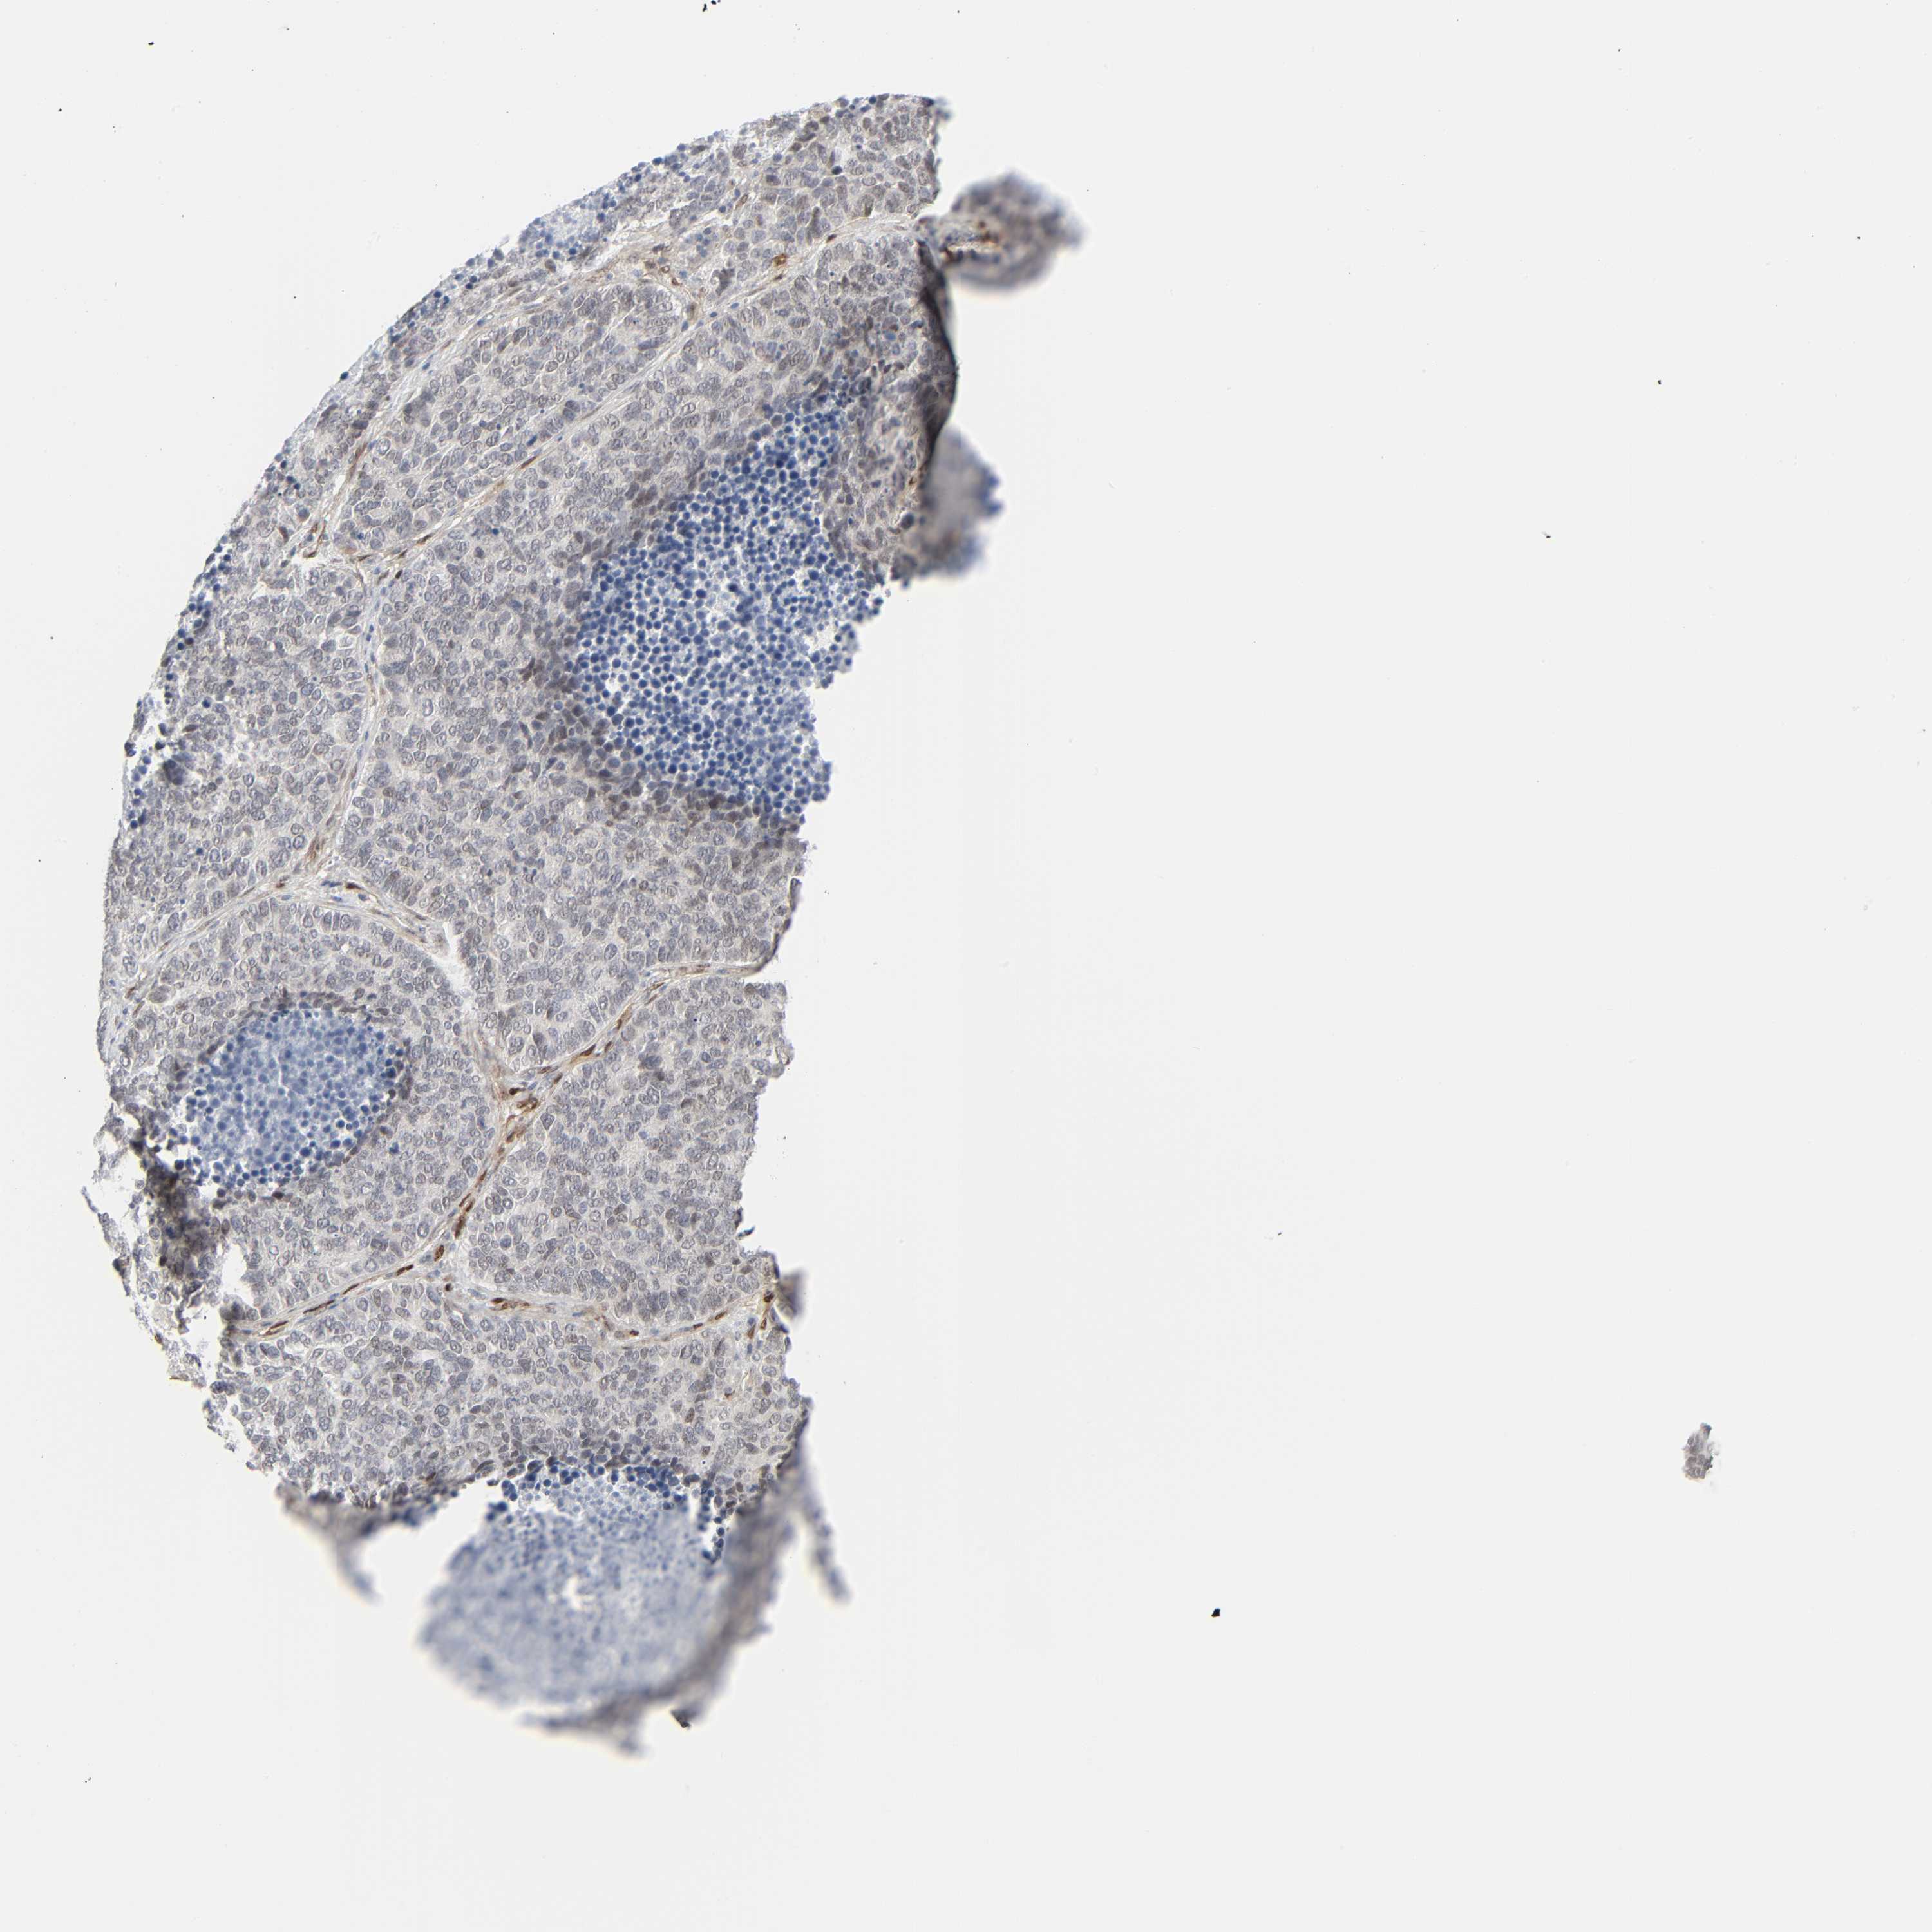

CANCER LUNG CANCER Show tissue menu

Lung cancer

Human cancer

Lung adenocarcinoma

Lung squamous cell carcinoma